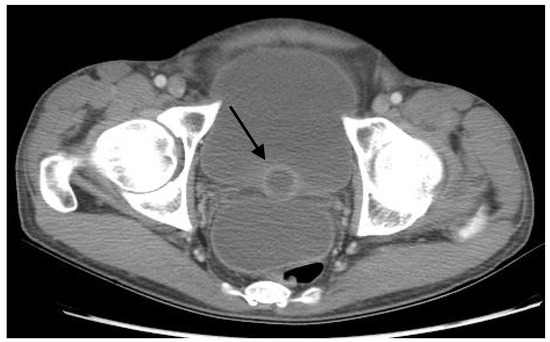

Tuberculous Prostate Abscesses in an Immunocompetent Patient: A Dramatic Presentation of Disseminated Tuberculosis

Genitourinary tuberculosis (TB) is infrequently reported in the United States, but is a common form of extrapulmonary TB that often goes unnoticed due to its insidious and sometimes asymptomatic presentation. Prostate involvement and the development of tuberculous prostatic abscesses have been reported in the literature largely in association with human immunodeficiency virus (HIV) infection and acquired immunodeficiency syndrome (AIDS). We report a case of disseminated TB involving tuberculous prostatic abscesses in a patient without HIV/AIDS, presenting with sepsis and urinary symptoms. This patient had simultaneous prostatic, peritoneal, pulmonary, and likely renal TB, serving as a reminder to clinicians that multi-organ presentations of TB do occur in patients without overt immunosuppressive conditions. This case also highlights the importance of considering the diagnosis of genitourinary TB in patients with risk factors for TB presenting with vague, long-standing urinary symptoms. Full article